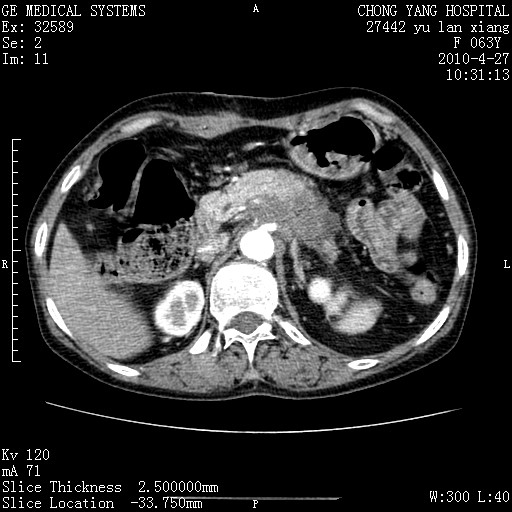

标题: CT26066:F63Y 上腹正中压痛半月,CA199:7400u/ml,MR示胰腺炎伴 [打印本页]

胰腺癌侵犯腹腔动脉干-分支、胃壁、左侧膈肌伴胰周及腹膜后淋巴结转移、胆囊切除术后。

胰腺癌侵犯腹腔动脉干-分支、胃壁、左侧膈肌伴胰周及腹膜后淋巴结转移、胆囊未显影。